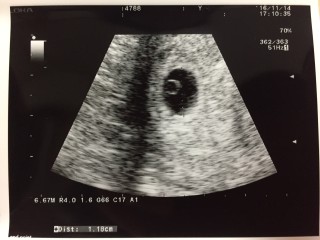

やっと待望の赤ちゃんです! 胎嚢10.1mm、胎芽2.5mmで、拡大するとなんとか心拍も見えました(o^^o) 頑張って大きくなってね!

前回の診察で3㎜しかなかった胎嚢が一週間で11.6㎜と成長してくれてました(>_<)胎嚢の中にもホワイトリングが見えます!でも、心拍確認はできませんでした。来週心拍確認できますように☆